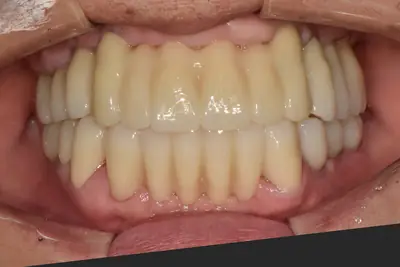

치과 치료를 두려워하는 분들을 위해, 진정요법을 활용한 사례를 소개합니다. 부산에 거주하던 60대 여성 환자가 치아가 많이 손상되어 임플란트와 브릿지 치료를 받았는데, 병원 트라우마와 공포로 어려움이 있었어요. 의식하 진정요법을 통해 깊은 낮잠 같은 상태에서 안전하게 치료를 받았고, 수술 과정도 성공적이었어요. 이 방법은 전신마취보다 안전하고, 환자도 큰 두려움 없이 치료를 마칠 수 있어요. 치과 공포증이 심한 분들도 전문가와 상담 후 진정요법을 고려해보시면 좋겠습니다.